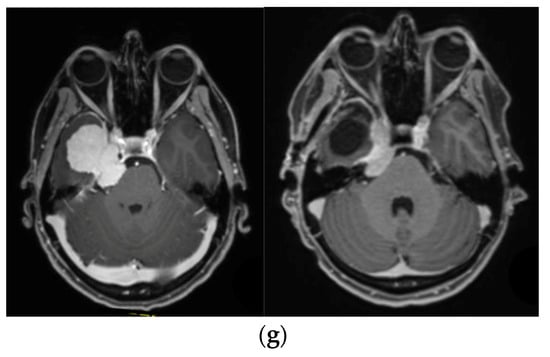

—right optic tract: mean dose marginally safe, max. dose unsafe. (f) Fusion of intraoperative CT to final intraoperative ISU. (g) Preoperative and 3 months postoperative MRI imaging for planning of radiosurgery (5 × 5 Gy).

—right optic tract: mean dose unsafe, max. dose safe. (i) Comparison of pre- and 3 months postoperative MRI for stereotactic radiation planning. The residual tumor was finally treated with hypofractionated radiotherapy (5 × 5 Gy).